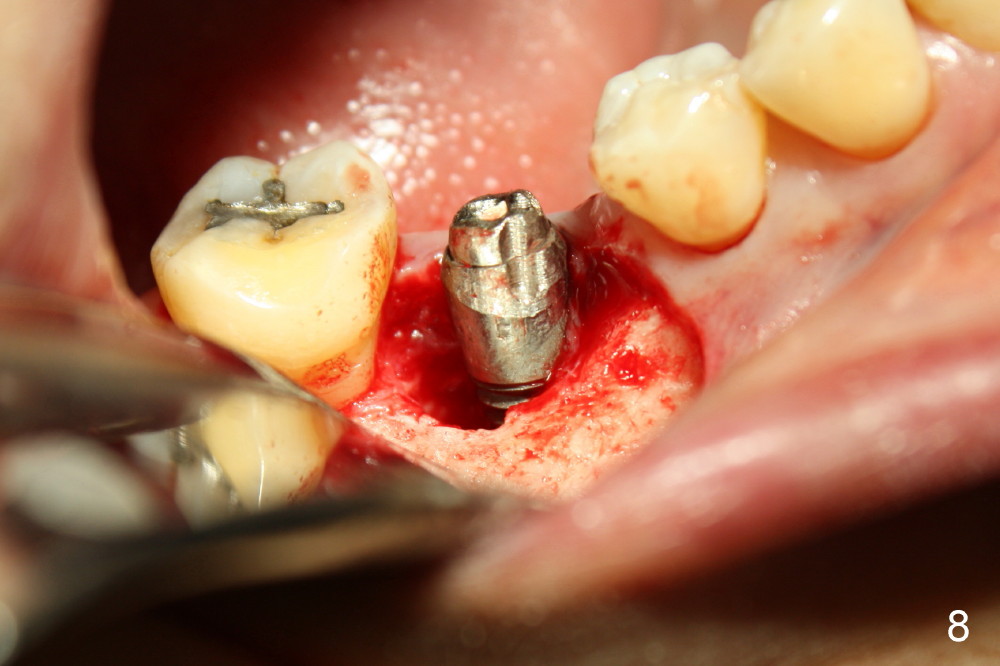

The infection may be related to chronic infection at the tooth #9. The latter is extracted, but the infection at the site of #30 does not resolve (Fig.5,6). The buccal flap is raised to reveal granulation tissue distobuccal to the implant (Fig.7). Bony defect and implant thread exposure are shown after debridement (Fig.8). Irradiated cancellous bone graft is placed to the defect (Fig. 9, Rocky Mountain Tissue Bank). The flap is closed with relative tension free. The definitive crown is temporarily cemented. The graft is exposed with no infection 2 week post grafting (Fig.10). The distobuccal defect appears to have healed 5 months post grafting (Fig.11) and the crown is permanently cemented (Fig.12). There is no buccal bone resorption, probably associated with immediate implantation. The patient remains asymptomatic 13 months postop.